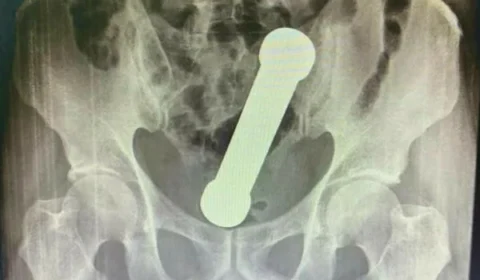

Para satisfação sexual, paciente fica com peso de academia preso no corpo em Manaus

Paciente de Manaus precisou de cirurgia após introduzir peso de academia no corpo para obter satisfação sexual.